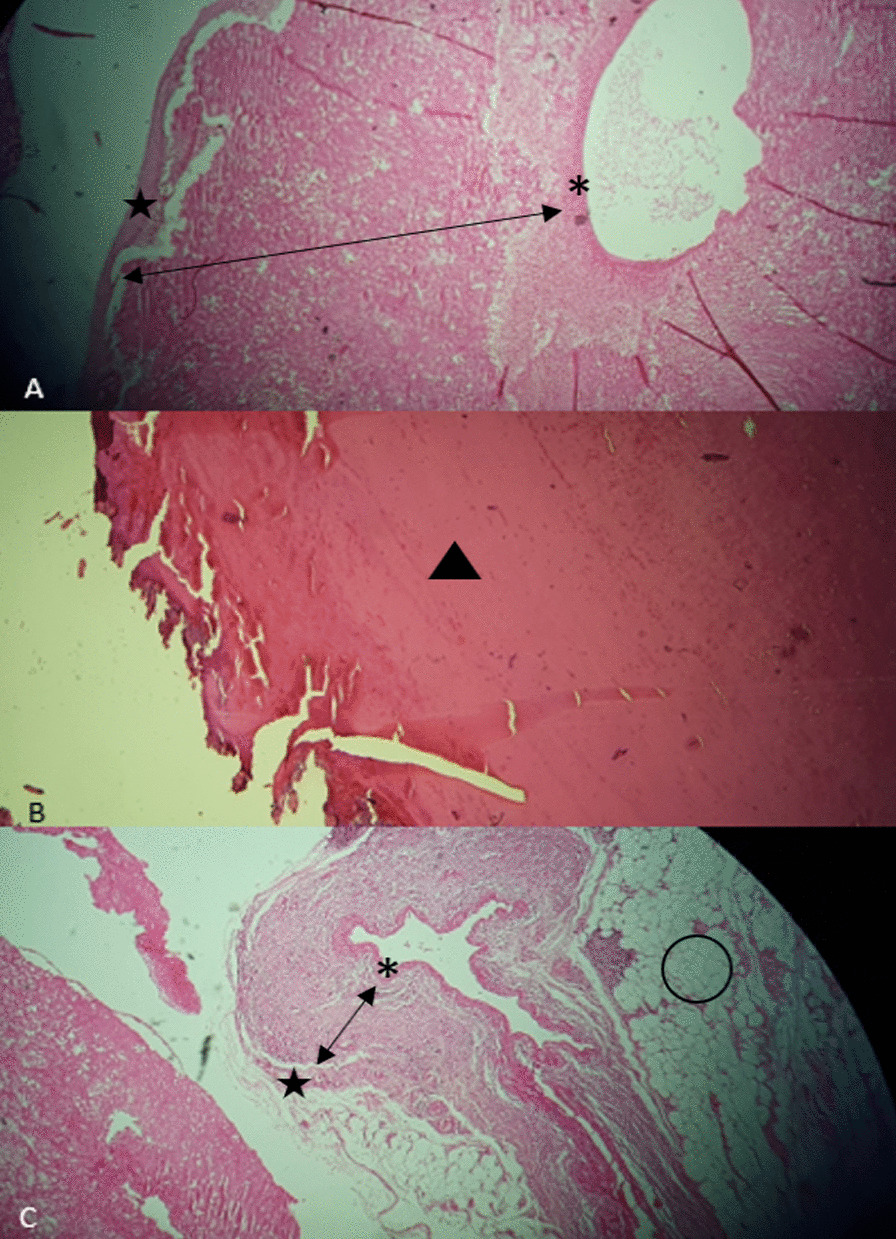

Finally, transection of MAL and peri-arterial tissue was performed, and decompression of the celiac axis was done. After the division of MAL, blood flow was restored in the proper hepatic artery by palpation. In the end, the abdominal wall was repaired, and the patient was transferred to the recovery room and then surgery ICU. The next day after surgery, the patient suffered a sudden drop in blood pressure and shock and unfortunately passed away. Pathology of resected aneurysms confirmed the presence of all three layers of the arterial wall and the absence of inflammatory infiltrates, fibrinoid necrosis, or evidence of vasculitis in the arterial wall (Fig. 4). Unfortunately, the patient’s family did not consent to an autopsy, but the most likely cause of death was hemorrhagic shock due to a blow out of a ligated artery in frail perivascular tissues.